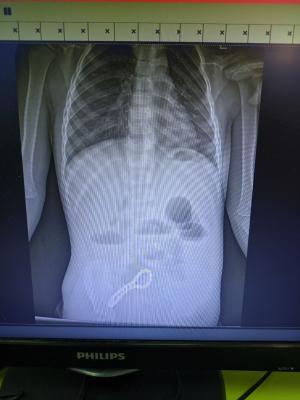

Когда родители ребёнка заметили очевидные нарушения работы желудочно-кишечного тракта сына, его госпитализировали в ОДКБ. Хирурги заподозрили нарушение функций кишечника, а рентгенограмма подтвердила предположения. Диагноз — инородное тело в кишечнике, которое нужно было удалять.

«Было принято решение об операции. Мы провели минилапаротомию (хирургическое вмешательство, при котором через разрез передней брюшной стенки производится доступ к внутренним органам живота). И увидели, что магнитами, которые притянулись друг к другу, соединены петли кишки, в её стенке — отверстия. В ходе операции удалили 30 магнитных бусин: 29 маленьких и одну большую. Сейчас ребёнок поправился. Его жизни и здоровью ничего не угрожает», — сообщил заведующий детским хирургическим отделением ОДКБ имени Дмитриевой Олег Ларькин.